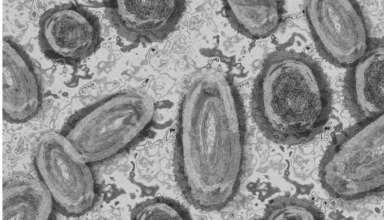

Самая обсуждаемая новость последних дней –коронавирус в России «отменили»! Даже не дожидаясь понедельника, ещё 1 июля, Роспотребнадзор объявил о снятии всех ограничений, введённых на территории нашей страны из-за пандемии ковида. А всё потому, чтов течение последних четырёх месяцев наблюдается«устойчивое снижение интенсивности эпидемического процесса по Cоvid-19», а почти все подтверждённые случаи коронавирусной инфекции среди россиян протекают в лёгкой форме, а то и вовсе бессимптомно! Однако стоит отметить, что в настоящее время коронавирусом заражаются гораздо больше людей, чем в начале пандемии, когда были введены …